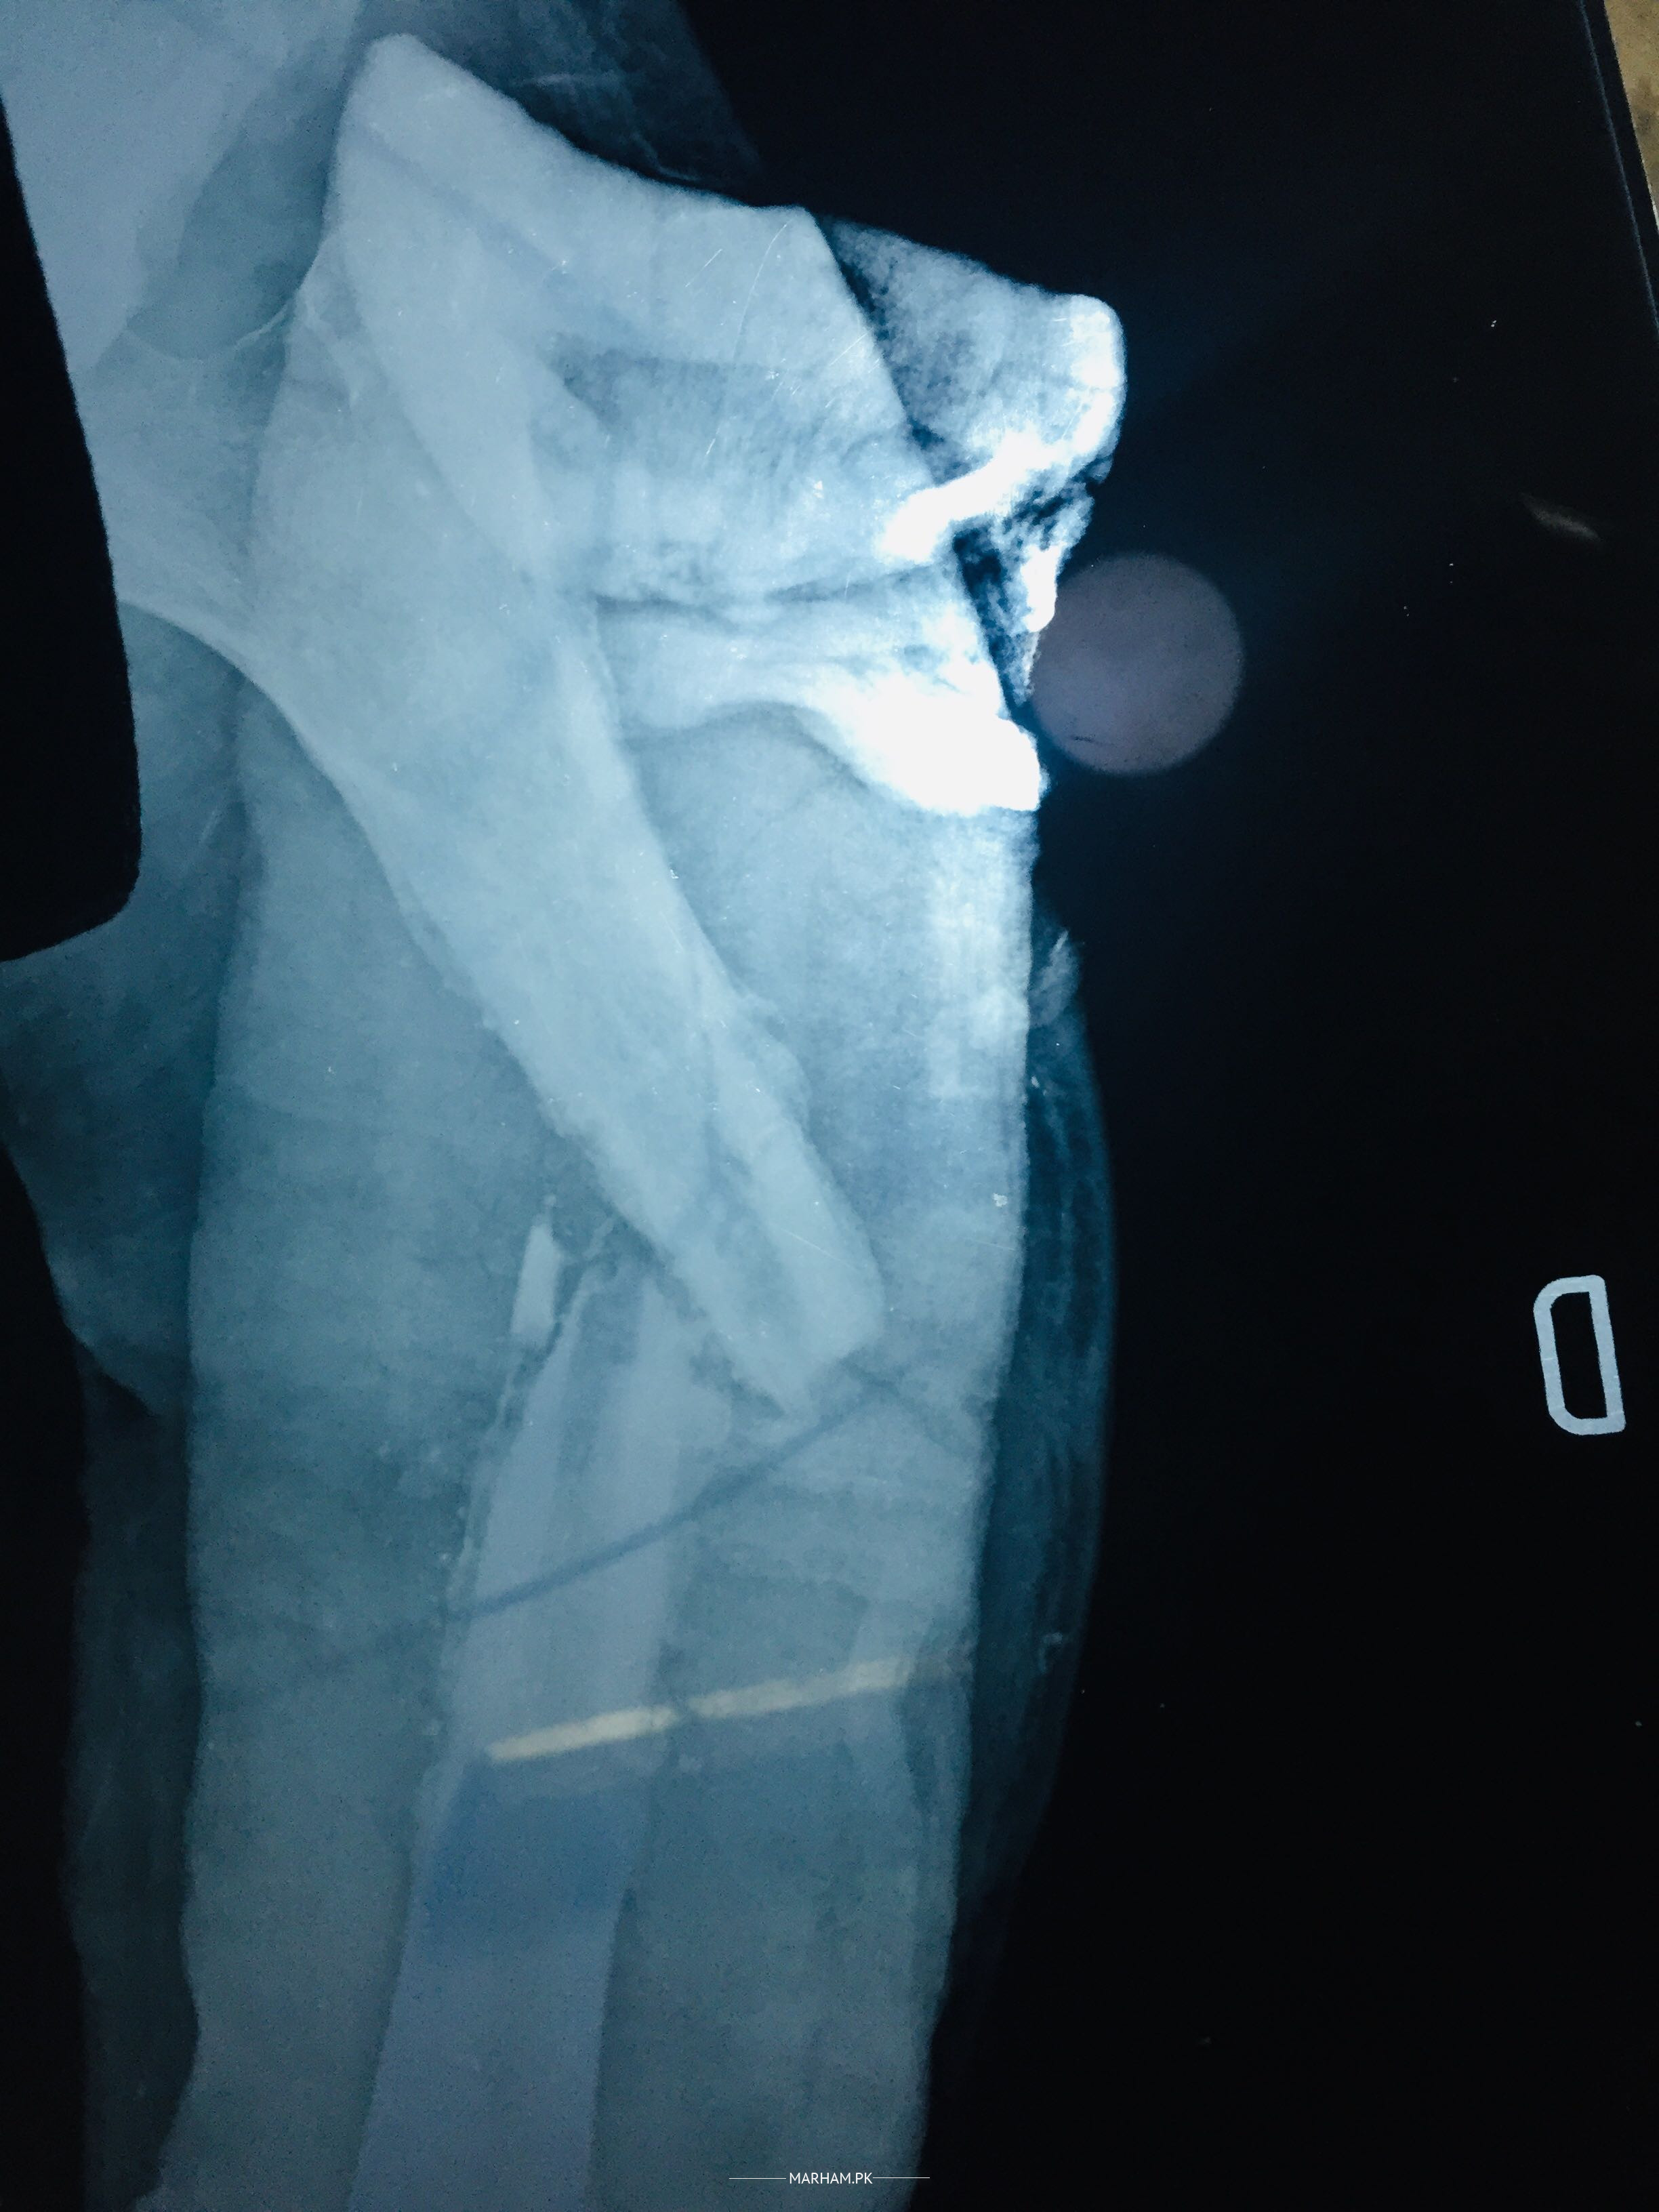

Meri bone fracture ho ge thi doctor na opreat kar k tik kar di thi ab bone zyada khrab halat ma ho ge ha ma share kar rha ho report mra Protein C.R.P level 59.8mg/L ha im sharing my xray and rports jab ono na old suergory wala fixator nikala to ya hal ho gya meri bone ka phla sa b zyada khrab ho ge

You will need a circular frame fixator and the treatment will take long time. Is there any discharge from the wound?

Infection is very bad for wound and bone healing.

ilizarov fixation plus tab fucidin 250 2tb TDS for 6weeks

soft tissues and skin condition is not good